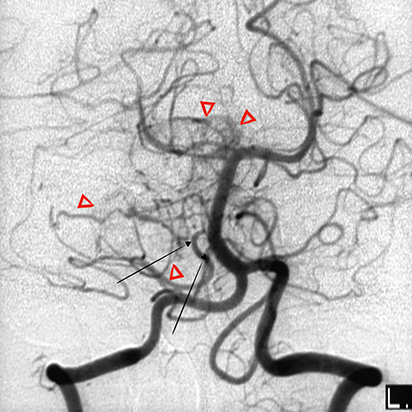

- Μπορεί να είναι πολλαπλά, ακόμη και εκτός της πλήρους έκφράσεως του συνδρόμου von Hippel Lindau. Εντοπίζονται στον οπίσθιο κρανιακό βόθρο ή τον νωτιαίο μυελό. Αν και είναι σαφώς αφοριζόμενοι όγκοι, στερούνται κάψας. Συχνά αντλούν αιμάτωση από την επαφή τους με το παρακείμενο εγκεφαλικό παρέγχυμα. Σε μερική αφαίρεση, υποτροπιάζουν συχνά. Δεν προκαλούν απομακρυσμένες μεταστάσεις.

- Τυπικά παρουσιάζονται λόγω χωροκατακτητικών σημείων με αύξηση της ενδοκρανίου πιέσεως και υδροκεφαλία από απόφραξη της 4ης κοιλίας. Σε μυελική εντόπιση, το εντοπισμένο άλγος με προϊούσα κινητικο-αισθητική διαταραχή, οδηγεί χωρίς θεραπεία σε παραπληγία ή τετραπληγία. Η αιμορραγία είναι σπάνια.

- Το σύνδρομο von Hippel Lindau, κληρονομείται κατά τον αυτοσωματικό επικρατούντα τύπο. Χαρακτηρίζεται από όγκους του ΚΝΣ και των κοιλιακών σπλάχνων, συνήθως αιμαγγειοβλαστώματα της παρεγκεφαλίδος, αμφιβληστροειδική αγγειομάτωση, καρκίνο του νεφρού, φαιοχρωμοκύττωμα, αιμαγγειοβλαστώματα του νωτιαίου μυελού. Η συσχέτιση αιμαγγειοβλαστώματος με το σύνδρομο von Hippel Lindau, είναι 10-20%.